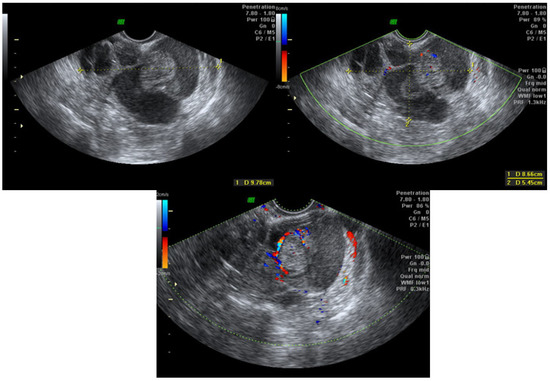

2.2. TVUS Evaluation of Adnexal Masses

- Van Holsbeke, C.; Van Calster, B.; Guerriero, S.; Savelli, L.; Paladini, D.; Lissoni, A.A.; Czekierdowski, A.; Fischerova, D.; Zhang, J.; Mestdagh, G.; et al. Endometriomas: Their ultrasound characteristics. Ultrasound Obstet. Gynecol. 2010, 35, 730–740. [Google Scholar] [CrossRef]